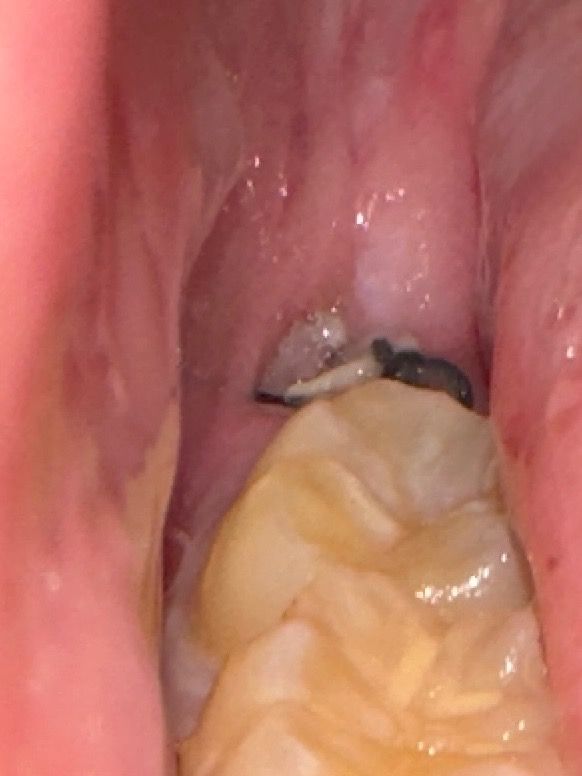

사랑니 발치 후 5일째인데 실밥이 헐렁해지더니 이물질? 잇몸뼈같은게 보이는데 정상인가요? 드라이소켓일 가능성은 없겠죠?

희게 보이는 것은 뽑은 자리 가장자리 잇몸에 딱지 앉은 것으로 보면 됩니다. 그냥두면 저절로 없어집니다.

잇몸뼈가 아니고 염증 육아조직 같습니다 치유과정에서 나오는 자연스러운 물질입니다 이물질 안 끼어있게 잘 헹궈주세요

사랑니 발치를 하고나서 잇몸이 치유되는 과정중에 생기는 자연스러운 현상이니 너무 걱정하지마세요.

해당 부분에서 잇몸뼈가 보이지는 않을 것이며 이물질 등일 겁니다. 염증소견은 안보입니다.

사랑니를 발치하고 나면 해당부위에 이물질등이 낄수 있습니다. 이물질을 제거하거나 하면 상처가 생기고 치유가 늦어 질수 있으니 가능하면 억지로 제거를 하려고 하지 않는것이 좋습니다.